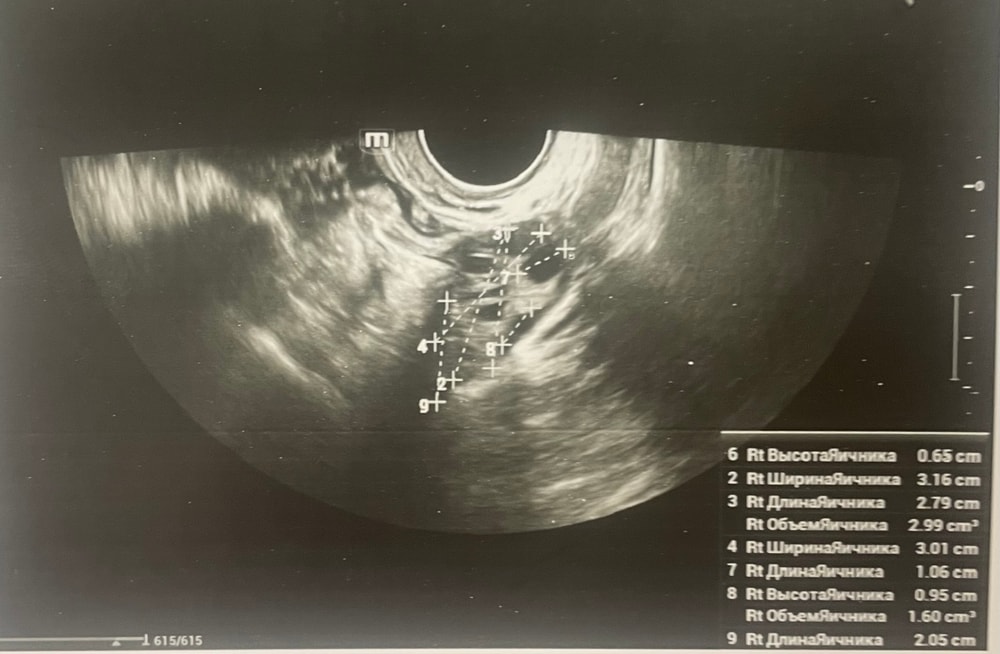

Прошу советаДобрый день, мы с мужем планируем беременность и в этом месяце произошло что то странное… дата начала последней менструации 4 октября закончилась 8, овуляцию отслеживала всю неделю почти сначала были бледные еле заметные полоски, 23 октября жирные четкие полоски, 24 октября стала чуть бледнее но яркая, вообщем положительный ещё был, с 25 числа тест уже отрицательный, через день после овуляции 26 числа стала странно себя чувствовать и во время овуляции болел живот то справа то с лева и поясница, так через день после начали болеть соски грудь вообще не болела, живот то болит то нет и с поясницей также, позже появилась небольшая изжога, нога немеет правая не знаю с чем связано), все это началось за 2 недели до месячных в середине цикла скажем так 29 числа пошла на узи спустя 6 дней грубо говоря гиня сказала что у меня была очень хорошая овуляция, что её признаки сохраняются до сих пор так скажем, желтое тело СПРАВО 20 мм, мои симптомы и все это очень похоже на беременность сказали большая вероятность, я очень была рада и надеялась, после узи появились выделения с комочками, до этого были просто густые белые выделения, утром тоже самое, пошла опять к гинекологу она сказала это может быть при ранец беременности сказала какие свечи купить, вечером я попала в не большое ДТП, удар был в поясницу и копчик, живот начал тянуть и поясница сильно болеть, начала болеть сама грудь помимо сосков, живот прошел относительно быстро, а вот поясница ломит до сих пор, решила сходить ещё раз на узи очень испугалась, на узи я пошла 31 через два дня после предыдущего и уже к другому гинекологу, моя на больничном, она сказала, что у меня отсутствуют даже косвенные признаки беременности и желтое тело с ЛЕВО А НЕ С ПРАВО, я не понимаю как такое может быть, очень расстроилась и совсем забыла про фото узи, она мне его не дала только заключение и как выяснилось уже не дадут оно не сохранилось, сказали переделывать, я очень доверяю своему гинекологу, но по заключению второго врача о беременности не может быть и речи в этом цикле, я не понимаю как желтое тело оказалось с лево если оно точно было справа в этом я уверена, а вторая врач уверяет во Братном, живот в обуляцию хоть и болел с двух сторон но больше справа помойму, вообщем я не понимаю есть ли шанс что я беременна или все таки нет, я понимаю что это слишком рано, до задержки ещё 4 дня, но мне плохо уже неделю по симптомам даже больше это же не просто так, я прикреплю фото заключения, могу ли я быть беременна, если посмотреть на эти заключения хотябы, подскажите пожалуйста фото узи относятся к 29.10, без фото 31.10